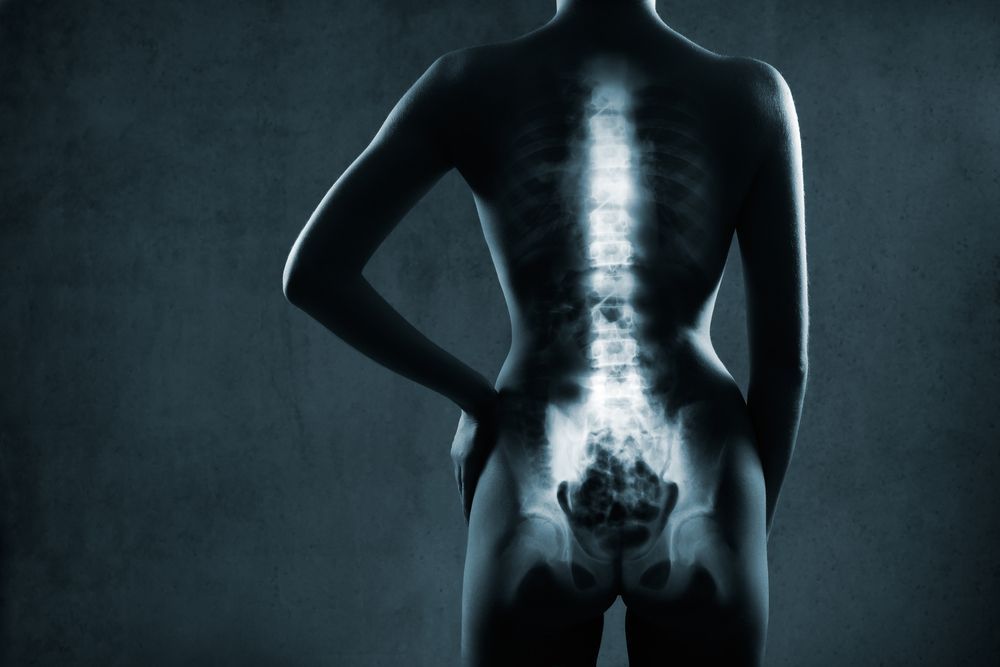

Axial spondyloarthritis (axSpA) is never a straightforward diagnosis. In this slideshow, we highlight 11 disease manifestations associated with axSpA.